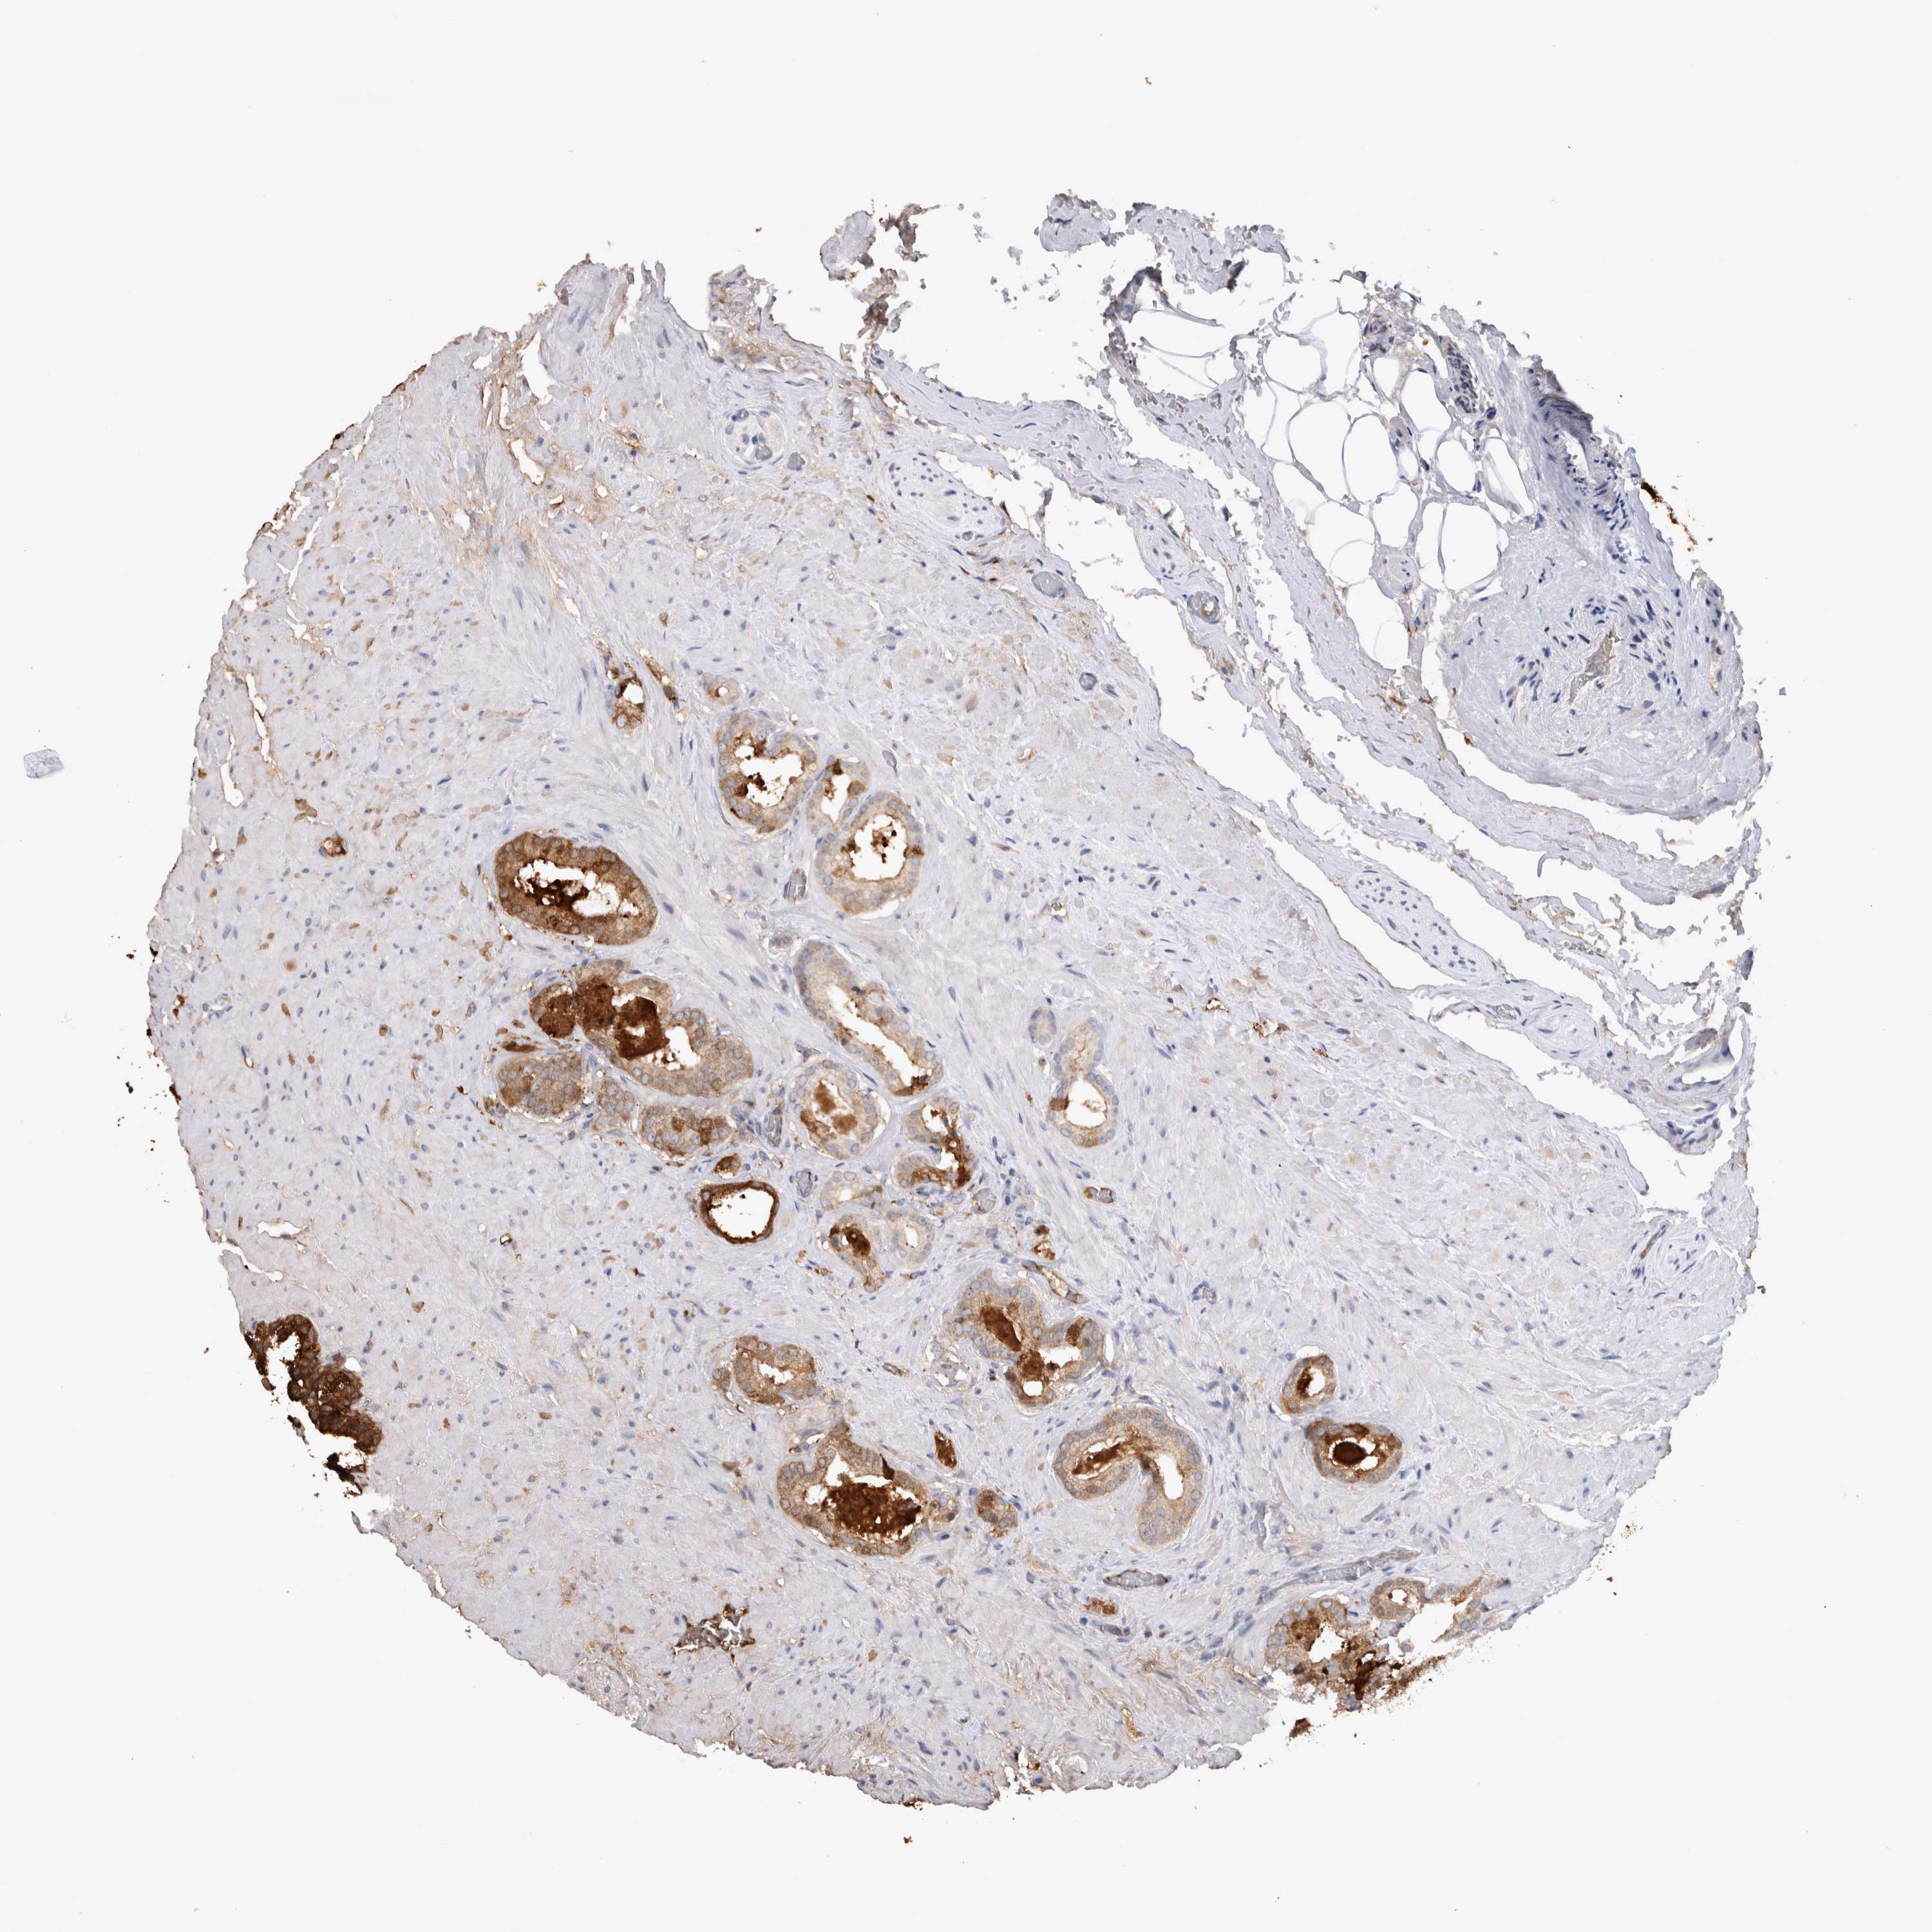

PROSTATE CANCER - Protein expressioni

A mouse-over function shows sample information and annotation data. Click on an image to view it in a full screen mode. Samples can be filtered based on level of antibody staining by selecting one or several of the following categories: high, medium, low and not detected. The assay and annotation is described here.

Antibody stainingi

Antibody staining in the annotated cell types in the current human tissue is reported as not detected, low, medium, or high, based on conventional immunohistochemistry profiling in selected tissues. This score is based on the combination of the staining intensity and fraction of stained cells.

Each image is clickable and will lead to virtual microscopy that enables deeper exploration of all samples and also displays staining intensity scores, fraction scores and subcellular localization as well as patient and tissue information for each sample.

Antibody HPA051257

Antibody CAB026357

Staining

High

Medium

Low

Not detected

Intensity

Strong

Moderate

Weak

Negative

Quantity

>75%

75%-25%

<25%

None

Location

Nuclear

Cytoplasmic/membranous

Cytoplasmic/membranous,nuclear

Adenocarcinoma, High grade

Adenocarcinoma, Medium grade

Adenocarcinoma, Low grade